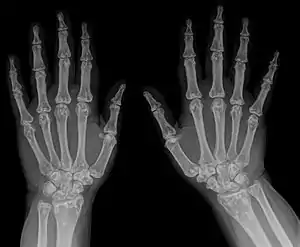

| Osteopoikilosis results in multiple enostoses. | |